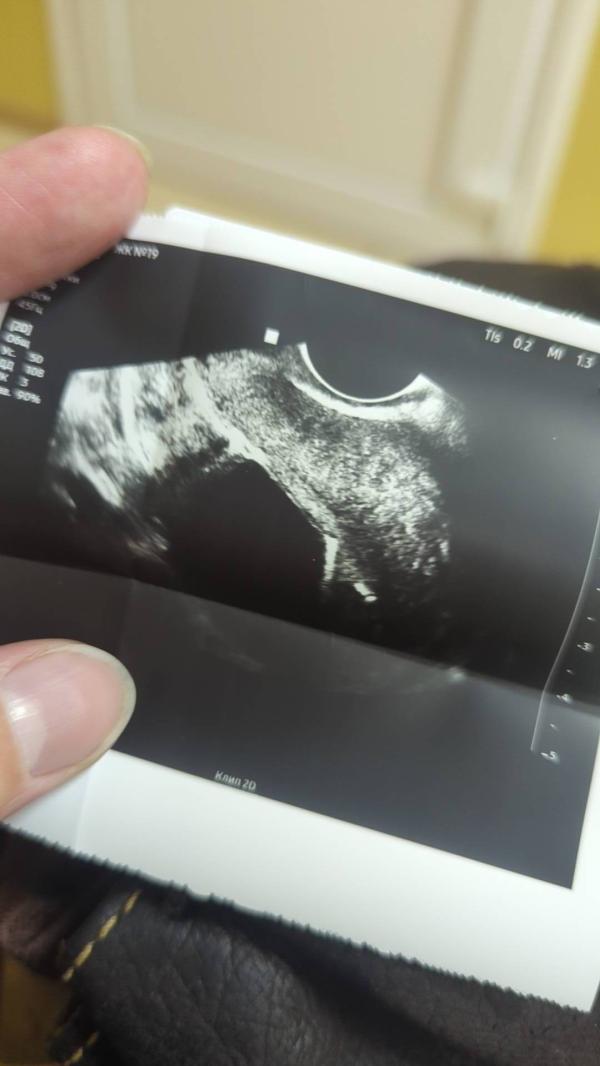

всё быстро, неприятно, но не больно. ставил доктор мужчина. сразу сделал УЗИ, посмотреть - встала как родная🤣

P.S. на УЗИ моя дорогая спираль 🤣 пост носит исключительно юмаристическо-жизнеутверждающий характер 😋🐈⬛